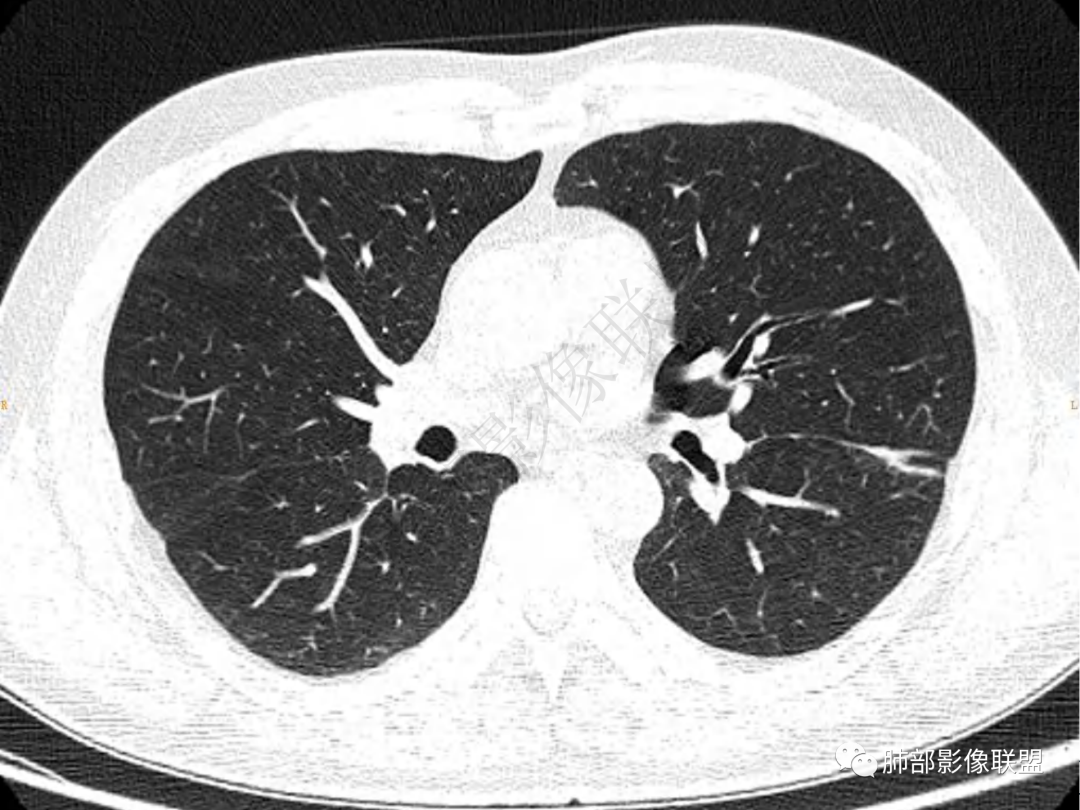

2.左肺下叶团片影,跨背段及内前基底段,实性部分类椭圆形,密度不甚均匀,可见毛刺及棘状突起,未见典型分叶及胸膜凹陷。病灶上下缘可见相应肺段支气管旁进侧出,管壁轻度增厚,未见狭窄阻塞。

3.周边较大范围磨玻璃影,边界相当模糊,小叶增厚明显。注意叶裂另一侧、左肺舌段亦可见磨玻璃影及增厚的小叶间隔。未见明确卫星病灶。

4.实性部分不均匀环形强化并显示一小范围低密度坏死区或空洞。较之肺窗,整体纵隔窗范围较小,提示病灶并不十分密实。抑或为不同时段图像。

肺脓肿:可宽基底与胸膜相连,附近胸膜增厚——炎性特点

肺脓肿:边界模糊不清,或者块影为类圆形,无明显分叶,边缘平直为主,刀切征——炎性特点三、病灶周围特点:肺脓肿:病灶非远端有片状GGO——炎性特点四、近端支气管阻塞:肺脓肿:常有引流支气管伴管壁增厚或者支气管沿洞壁走行。五:坏死壁:肺脓肿:大多壁厚,少数壁薄,没有壁结节,内壁清楚光整——炎性特点

肺脓肿:环形强化,强化较显著。如出现明显囊壁样强化甚至边缘“憩室”样突出,高度支持肺脓肿。